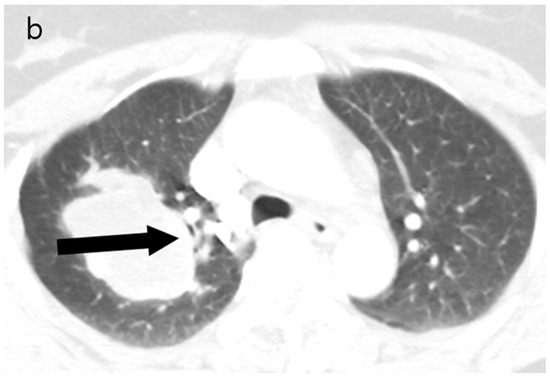

The patient’s postoperative period was uneventful, and she was discharged and subsequently administered chemotherapy. However, three months later, the patient was readmitted with left-sided hemiparesis. Brain MRI revealed a 25 mm T2-high signal and T1-low signal intensity mass with perilesional edema and faint peripheral enhancement in the posterior portion of the right superior frontal gyrus (Figure 6). Stereotaxic biopsy of the brain mass confirmed metastasis from the primary lung tumor. The metastatic brain tumor with hemorrhage was surgically removed, and the patient was started on chemotherapy and radiotherapy.

Nine months after the initial surgery, extensive metastatic lesions were detected in the lungs, adrenal glands, ribs, and erector spinae muscle. One month later, she was admitted to the emergency room with an altered mental status. Enhanced brain CT and MRI showed metastatic hemorrhagic tumors in the left temporal and right parietal lobes. Her condition continued to deteriorate, and two weeks later, she succumbed to respiratory arrest. This study was approved by the Institutional Review Board of our hospital (IRB No. Eulji 2023-12-015).